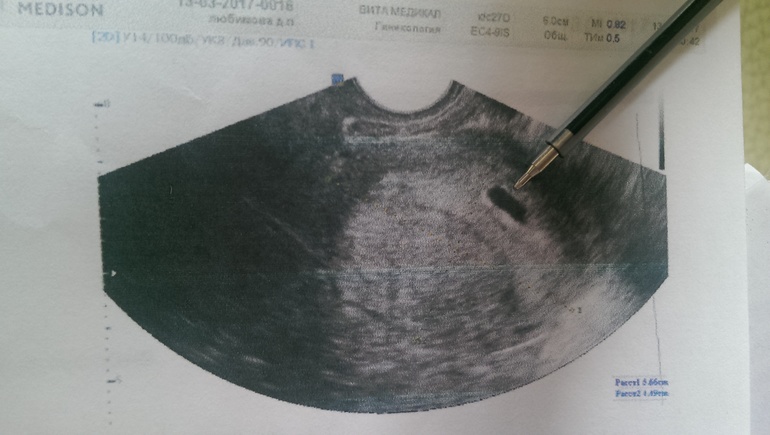

У меня тоже эмбриона не было, только желточный мешочек, но по его форме было ясно тонус или нет. То на что я указала ручкой должно быть идеально круглым без тонуса.